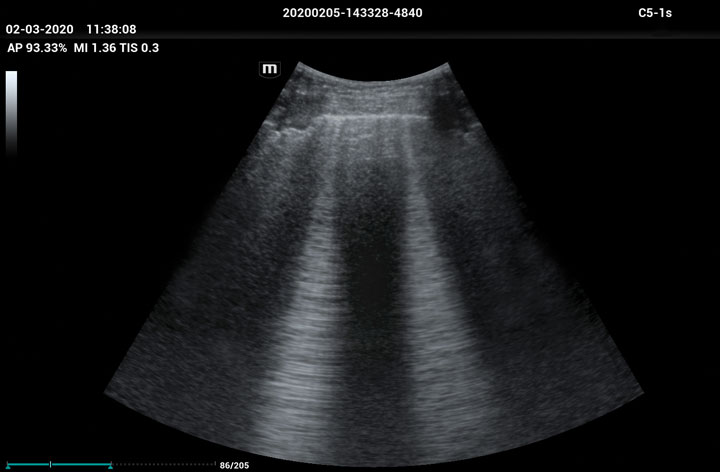

The ME8 Ultrasound System has been thoughtfully designed to overcome the obstacles clinicians face in today’s challenging healthcare environment. Powered by our groundbreaking software-based beamformer technology, ZONE Sonography® Technology+(ZST+), the ME8 Ultrasound System empowers decision-making by providing end-users best-in-class image quality and access to a comprehensive suite of workflow enhancement tools.